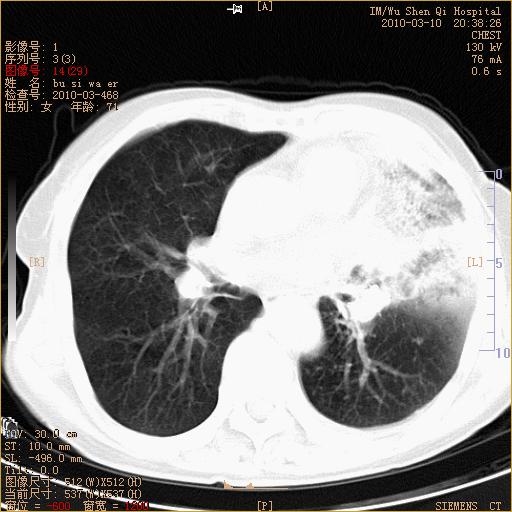

以下是引用随光逐影在2010-3-11 0:41:00的发言:[br]1)考虑左肺及右肺上叶继发性肺结核并左肺炎症感染。2)左侧支气管内膜结核可能;建议必要时行纤支镜检查。3)肺气肿。4)心包膜增厚(或少量心包积液)。5)左侧胸腔积液。